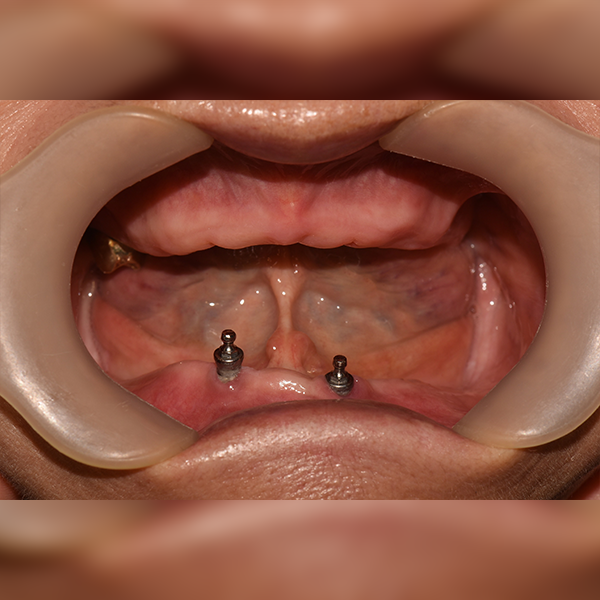

全顎/全体 / 骨移植|睡眠|糖尿病|アスピリン

症例.34 70代 アン*ジャ 2020-05-07 / 2021-01-10